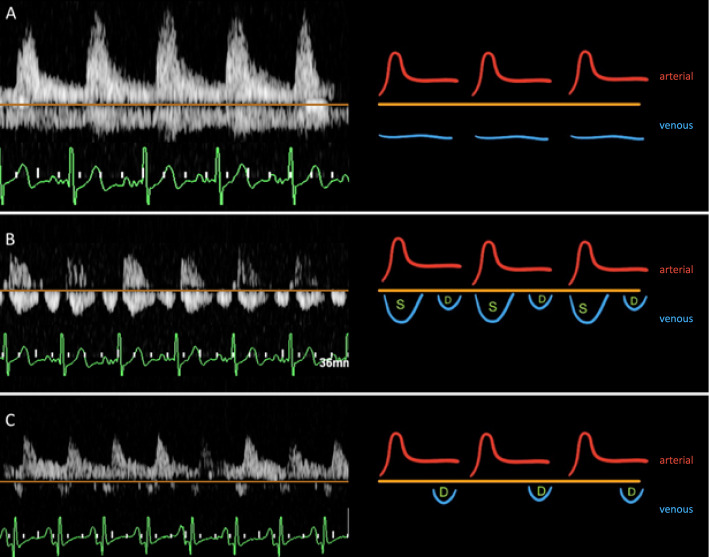

Background: Determining the optimal timing for fluid removal in critically ill patients remains a challenge. This study evaluated the utility of Doppler ultrasound, specifically intrarenal venous flow (IRVF) patterns and venous excess ultrasound (VExUS) scores, and their associations with fluid removal outcomes, hemodynamic parameters, and clinical endpoints.

Methods: In this prospective observational exploratory study, 52 intensive care unit (ICU) patients who underwent fluid removal were enrolled. Baseline IRVF patterns and VExUS scores were assessed, with follow-up evaluations performed daily for three days. The primary outcome was to evaluate whether IRVF patterns were associated with successful fluid removal, defined as achieving a negative fluid balance for at least two consecutive days. Secondary outcomes included associations with central venous pressure (CVP), NT-proBNP, cumulative fluid balance, and clinical outcomes.

Results: Thirty-one patients (59.6%) achieved successful fluid removal. A discontinuous baseline IRVF pattern was independently associated with successful fluid removal (adjusted odds ratio 4.31, 95% CI 1.02-18.18; P = 0.047). This pattern demonstrated high sensitivity of 87.1% (95% CI 70.2-96.4), moderate specificity of 42.9% (95% CI 21.8-66.0), and accuracy of 69.2% (95% CI 54.9-81.3). VExUS scores grades 2-3 demonstrated high specificity of 85.7% (95% CI 63.7-97.0) but low sensitivity of 29.0% (95% CI 14.2-48.0), with an accuracy of 51.9% (95% CI 37.6-66.0). An improvement in the IRVF pattern was significantly correlated with a reduction in NT-proBNP levels (P = 0.048). However, neither IRVF patterns nor VExUS scores improvements were associated with changes in fluid balance, CVP, or clinical outcomes such as 28-day mortality, ventilator-free days, or ICU length of stay.

Conclusions: Discontinuous IRVF patterns at baseline were significantly associated with fluid removal success, representing a physiologically based marker for deresuscitation readiness. More large-scale studies are warranted to validate these findings and explore long-term implications. Trial registration ClinicalTrials.gov identifier NCT06216119. Registered 22 January 2024, https://clinicaltrials.gov/study/NCT06216119.